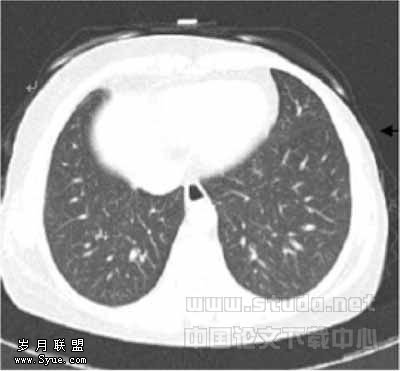

49例图像中,LD1与LD2扫描各有2例图像质量为良好(图1,2),其余均为优秀(图3,4),1例LD扫描图像比SD扫描图像清晰,原因是LD扫描时患者吸气充分而SD扫描时患者吸气不足。

图1,2分别为同一层面的常规剂量与低剂量CT,可见少量伪影,不影响观察肺结节图3,4分别为同一层面的常规剂量与低剂量CT图像,示未见伪影图3示小于5mm肯定肺结节(→?)和模糊肺结节(←?),图4分别显示为肯定(→?)、未见(←?)